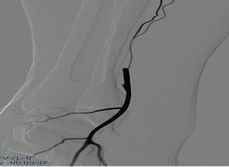

股淺動脈介入手術(shù)模塊

可練習(xí)股淺動脈支架手術(shù)的完整過程:造影診斷、導(dǎo)絲通過、導(dǎo)引導(dǎo)管的放置、預(yù)擴張、自擴張支架放置、后擴張、以及再造影等